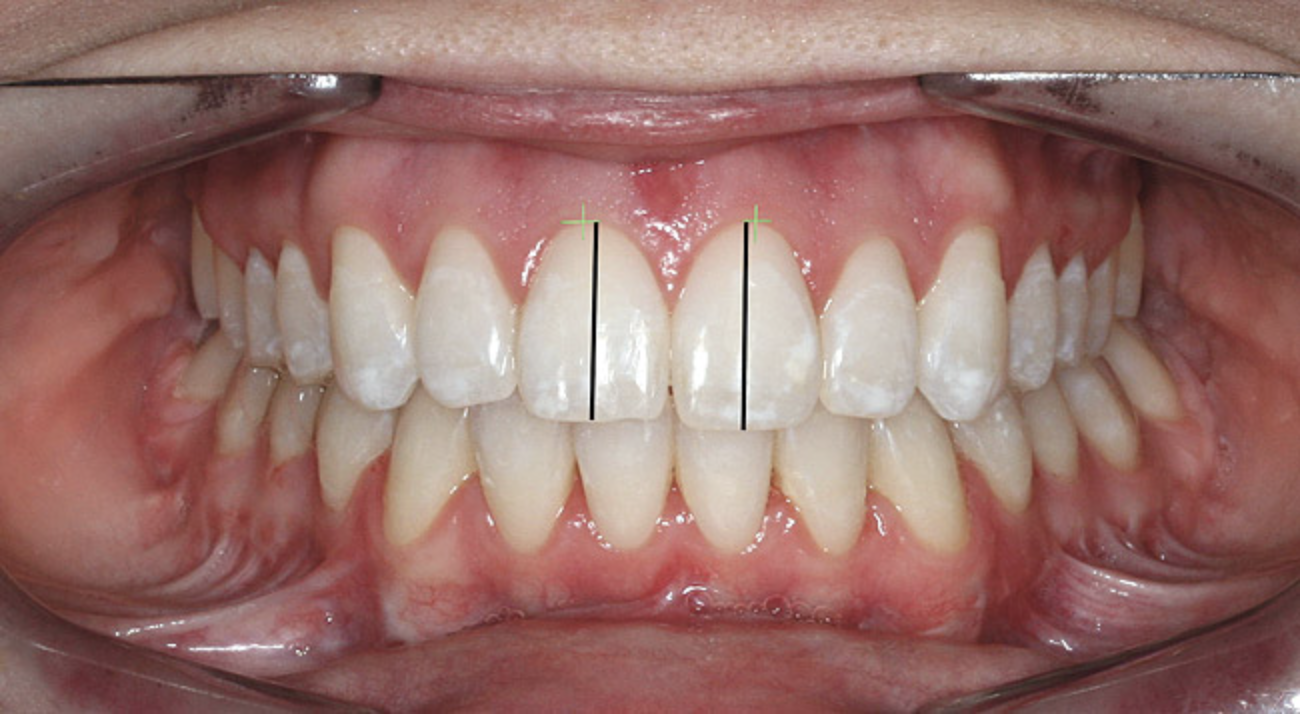

The dental midline can be improved within limits by restorative procedures. However, if orthodontic alignment is to be performed, the orthodontist plans treatment to ensure the position and vertical axis of the midline is harmonious with the facial esthetics (Figure 1).

The proportions of the teeth make a significant difference in the balance of the smile. Most restorative dentists are keenly aware of the importance of the golden proportion (Figure 2). When the maxillary lateral incisors are pegged or undersized, the orthodontist should be asked to redistribute the spaces. By positioning teeth properly, the restorative dentist can fabricate restorations to ideal proportions. When anterior teeth are crowded or broken down with loss of space, orthodontic alignment allows the natural proportions to be restored.

Figure 1  Dental midlines should be as close to coincident as possible. Gingival height of maxillary lateral incisors should be even with a line between the gingival height of the central incisor and canine to 1.5 mm below that line.

Figure 1

Figure 2   A balanced appearance of the anterior teeth is represented by a "golden proportional" of 1.618 for the maxillary central incisor, 1 for the lateral incisor, 0.618 for the canine.

Figure 2